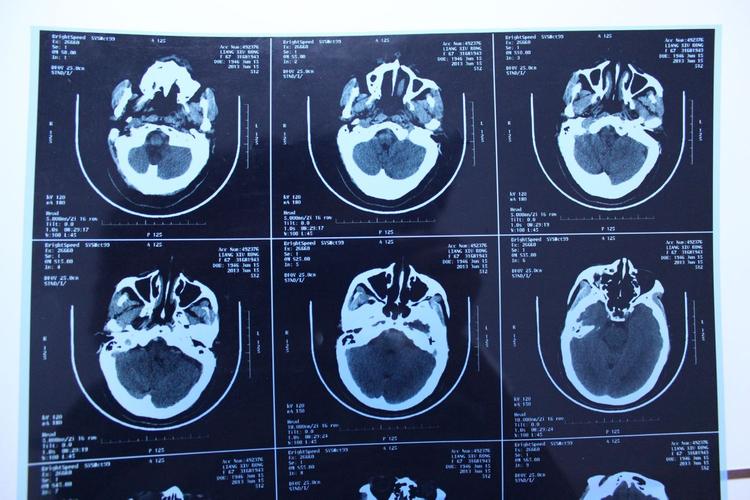

如何从图片上定位脑梗?

医生会通过MRI上的定位图来确定梗死的位置。

(图片来源网络,侵删)

- 横断面:像切面包一样,从头顶到脚底一层一层扫描,这是最常用的观察平面。

- 冠状面:像从正面给大脑拍一张X光片。

- 矢状面:像从侧面给大脑拍一张X光片。

通过这三个平面,医生可以精确地指出梗死灶位于大脑的哪个叶(如额叶、颞叶、顶叶、枕叶)、哪个脑区(如基底节区、丘脑、脑干、小脑),以及具体影响了哪些功能(如运动区、语言区等)。“左侧大脑中动脉供血区急性梗死”,就表明左侧大脑半球的很大一部分区域发生了缺血。